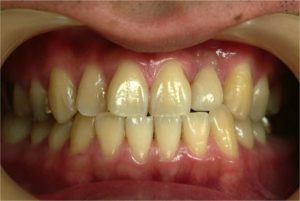

歯肉の状態もよく、セラミックのかぶせものをしました。

4年経ちましたが、大変良好な状態です(写真3)。

↑4年経過した状態ですが、歯の仕上がりの具合(色)もこの通りです。 セラミックの被せ物で、歯肉の状態も良好です。